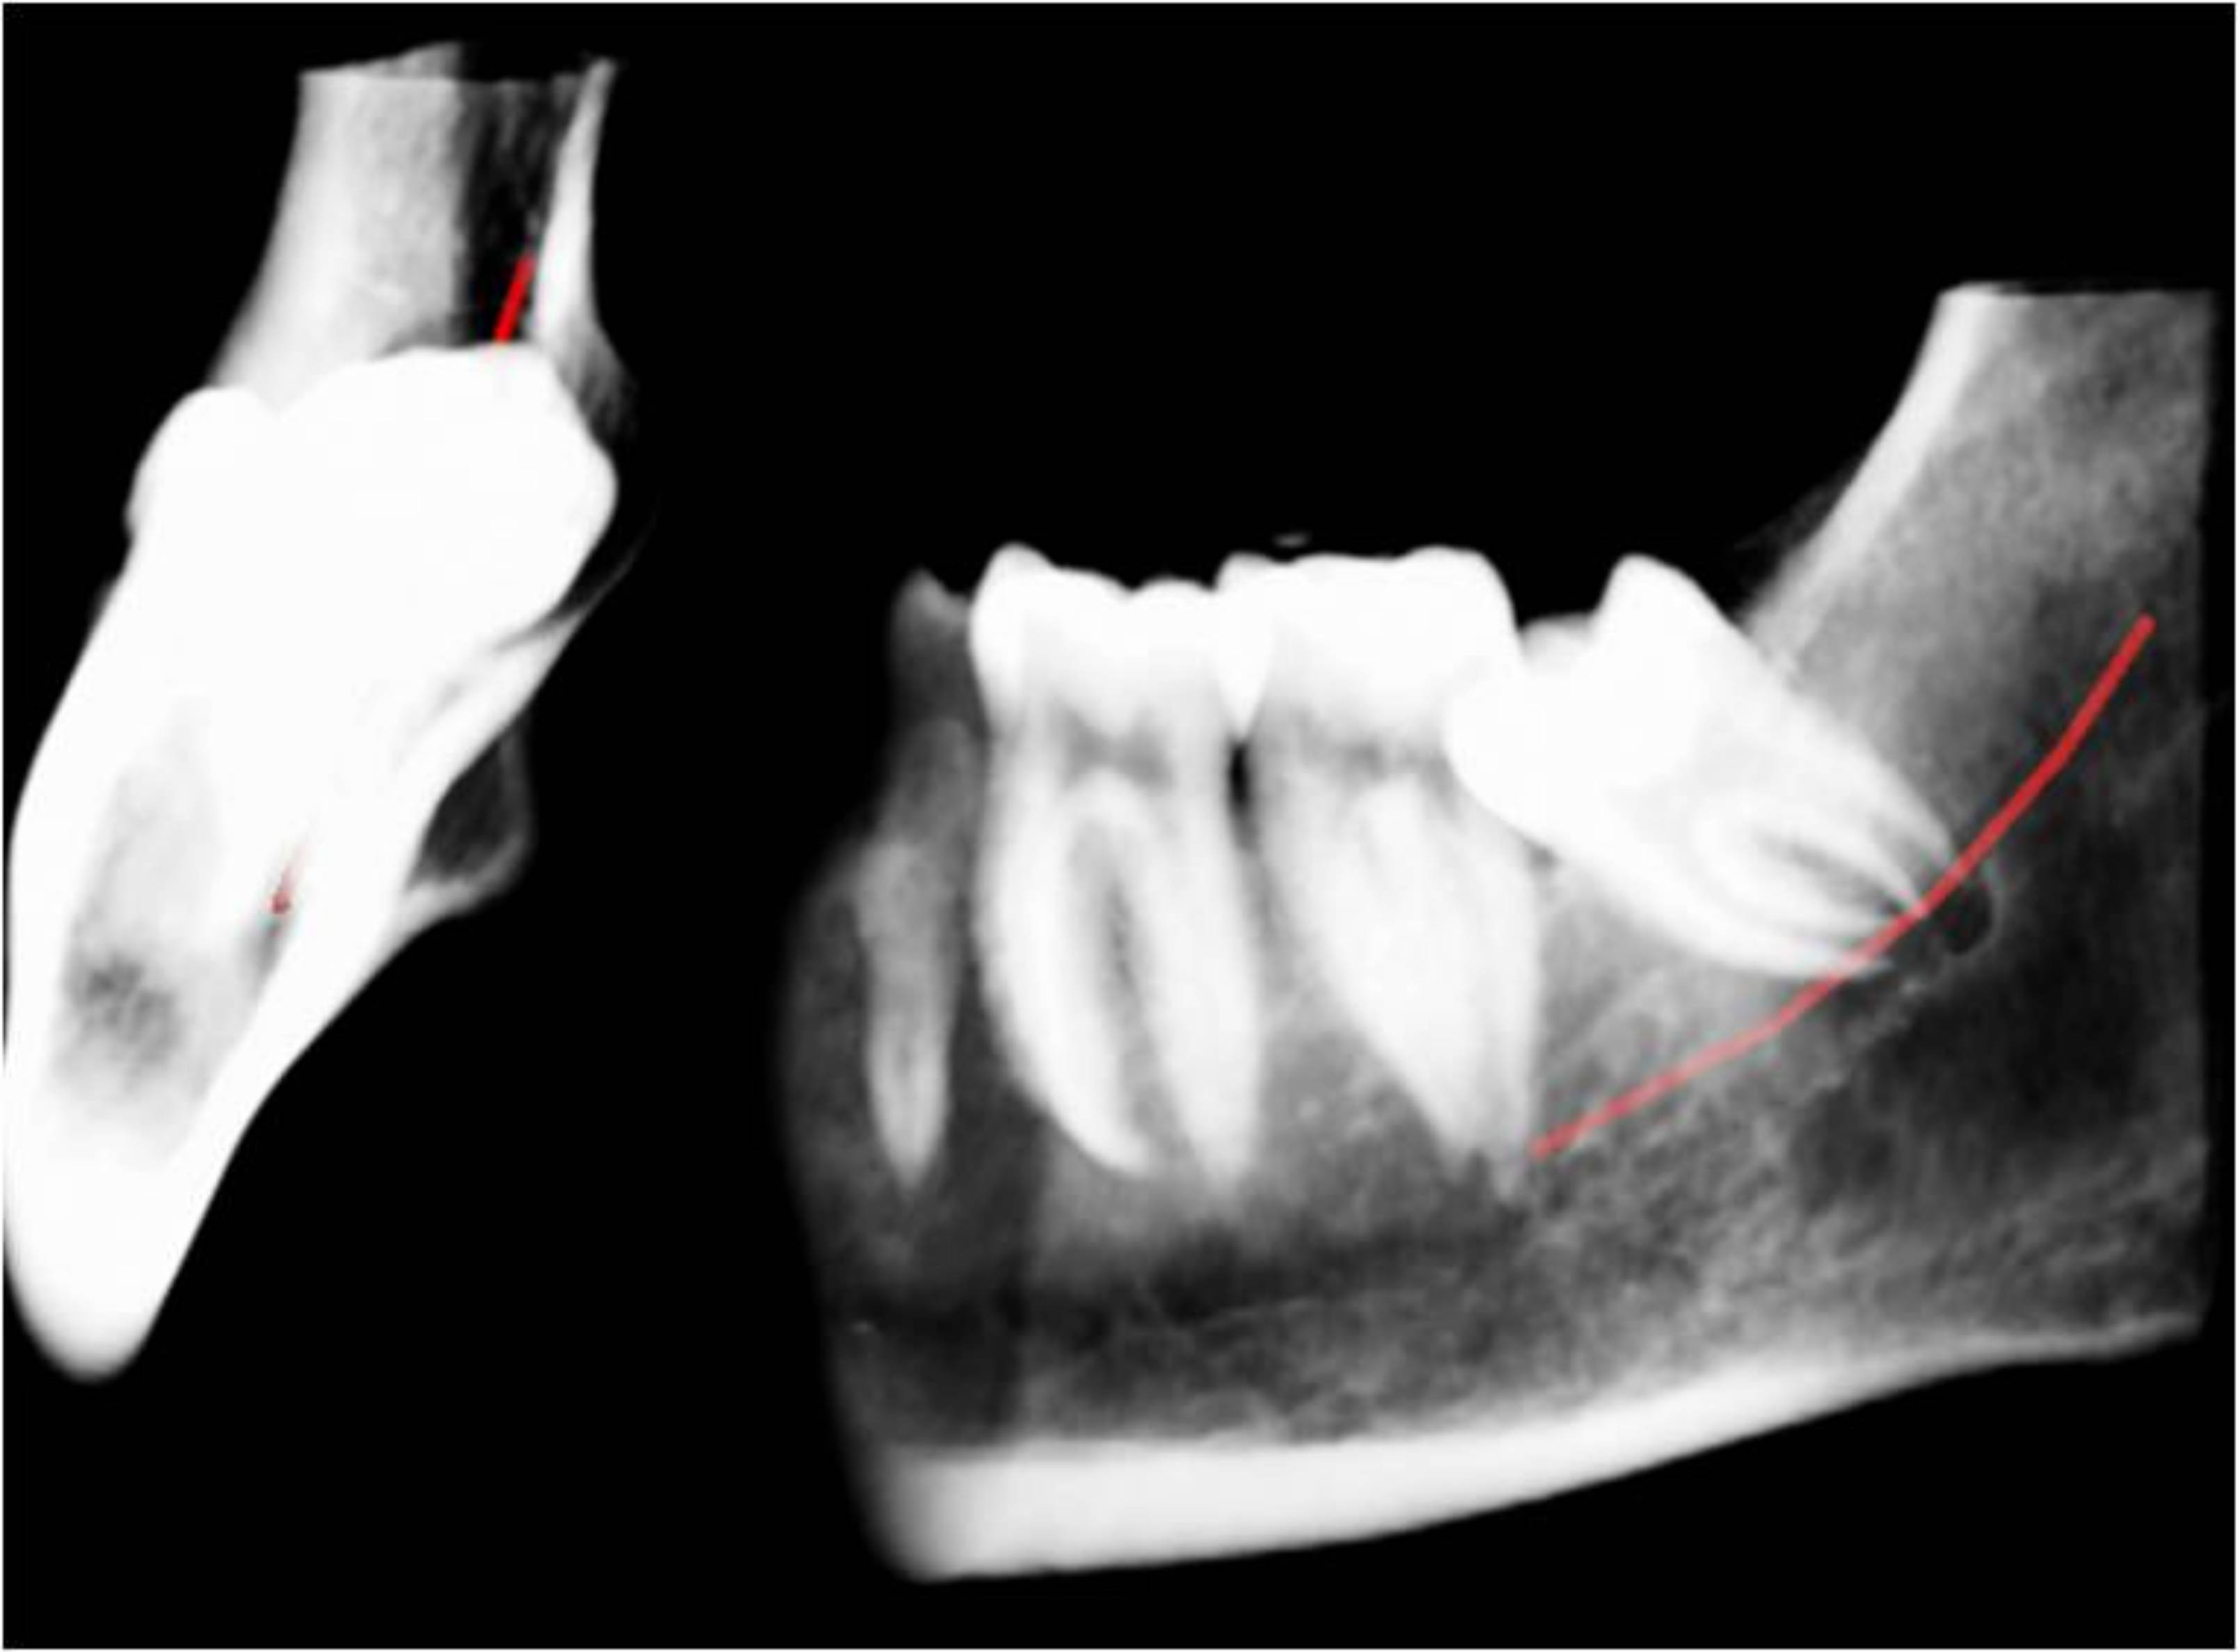

La correcta y clara identificación anatómica de las distintas estructuras comprendidas en la mandíbula son esenciales a la hora de programar una exodóncia de cordales.

De la proximidad de éstos con respecto al conducto dentario dependerá el éxito de la intervención. Nuestros estudios aportan la información en los tres planos radiológicos y herramientas para evitar posibles complicaciones, además de permititr obtener una visión real de todas las estructuras comprometidas en dicha intervención.

El examen radiológico siempre debería de preceder a la exodoncia simple o quirúrgica de un tercer molar cuando las estructuras circundantes pueden verse comprometidas.